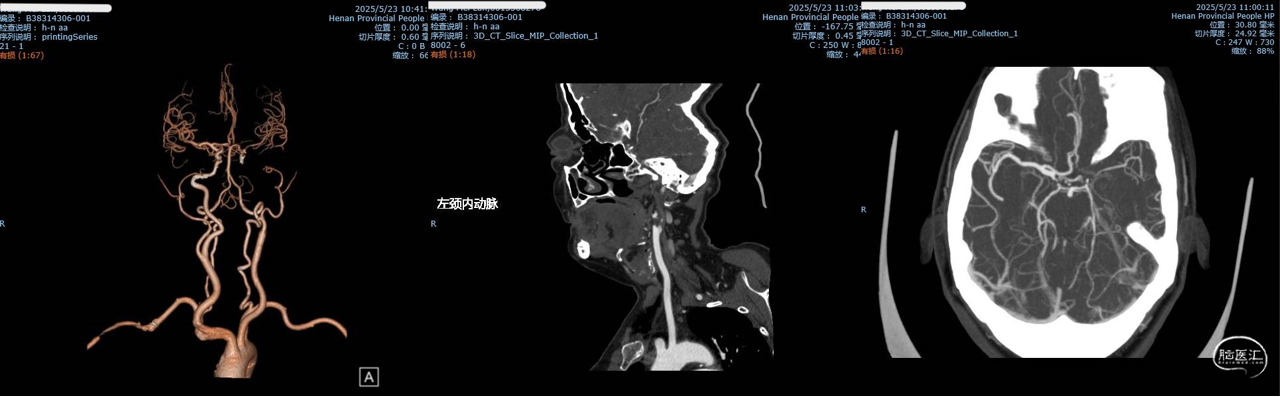

CTA提示左侧颈内动脉闭塞、大脑中动脉闭塞

DSA提示左侧颈内动脉闭塞,前交通未开放。

DSA提示大脑后动脉通过皮层动脉向前循环部分代偿。

PWI提示左侧额顶颞岛叶灌注延迟并脑血流减低。